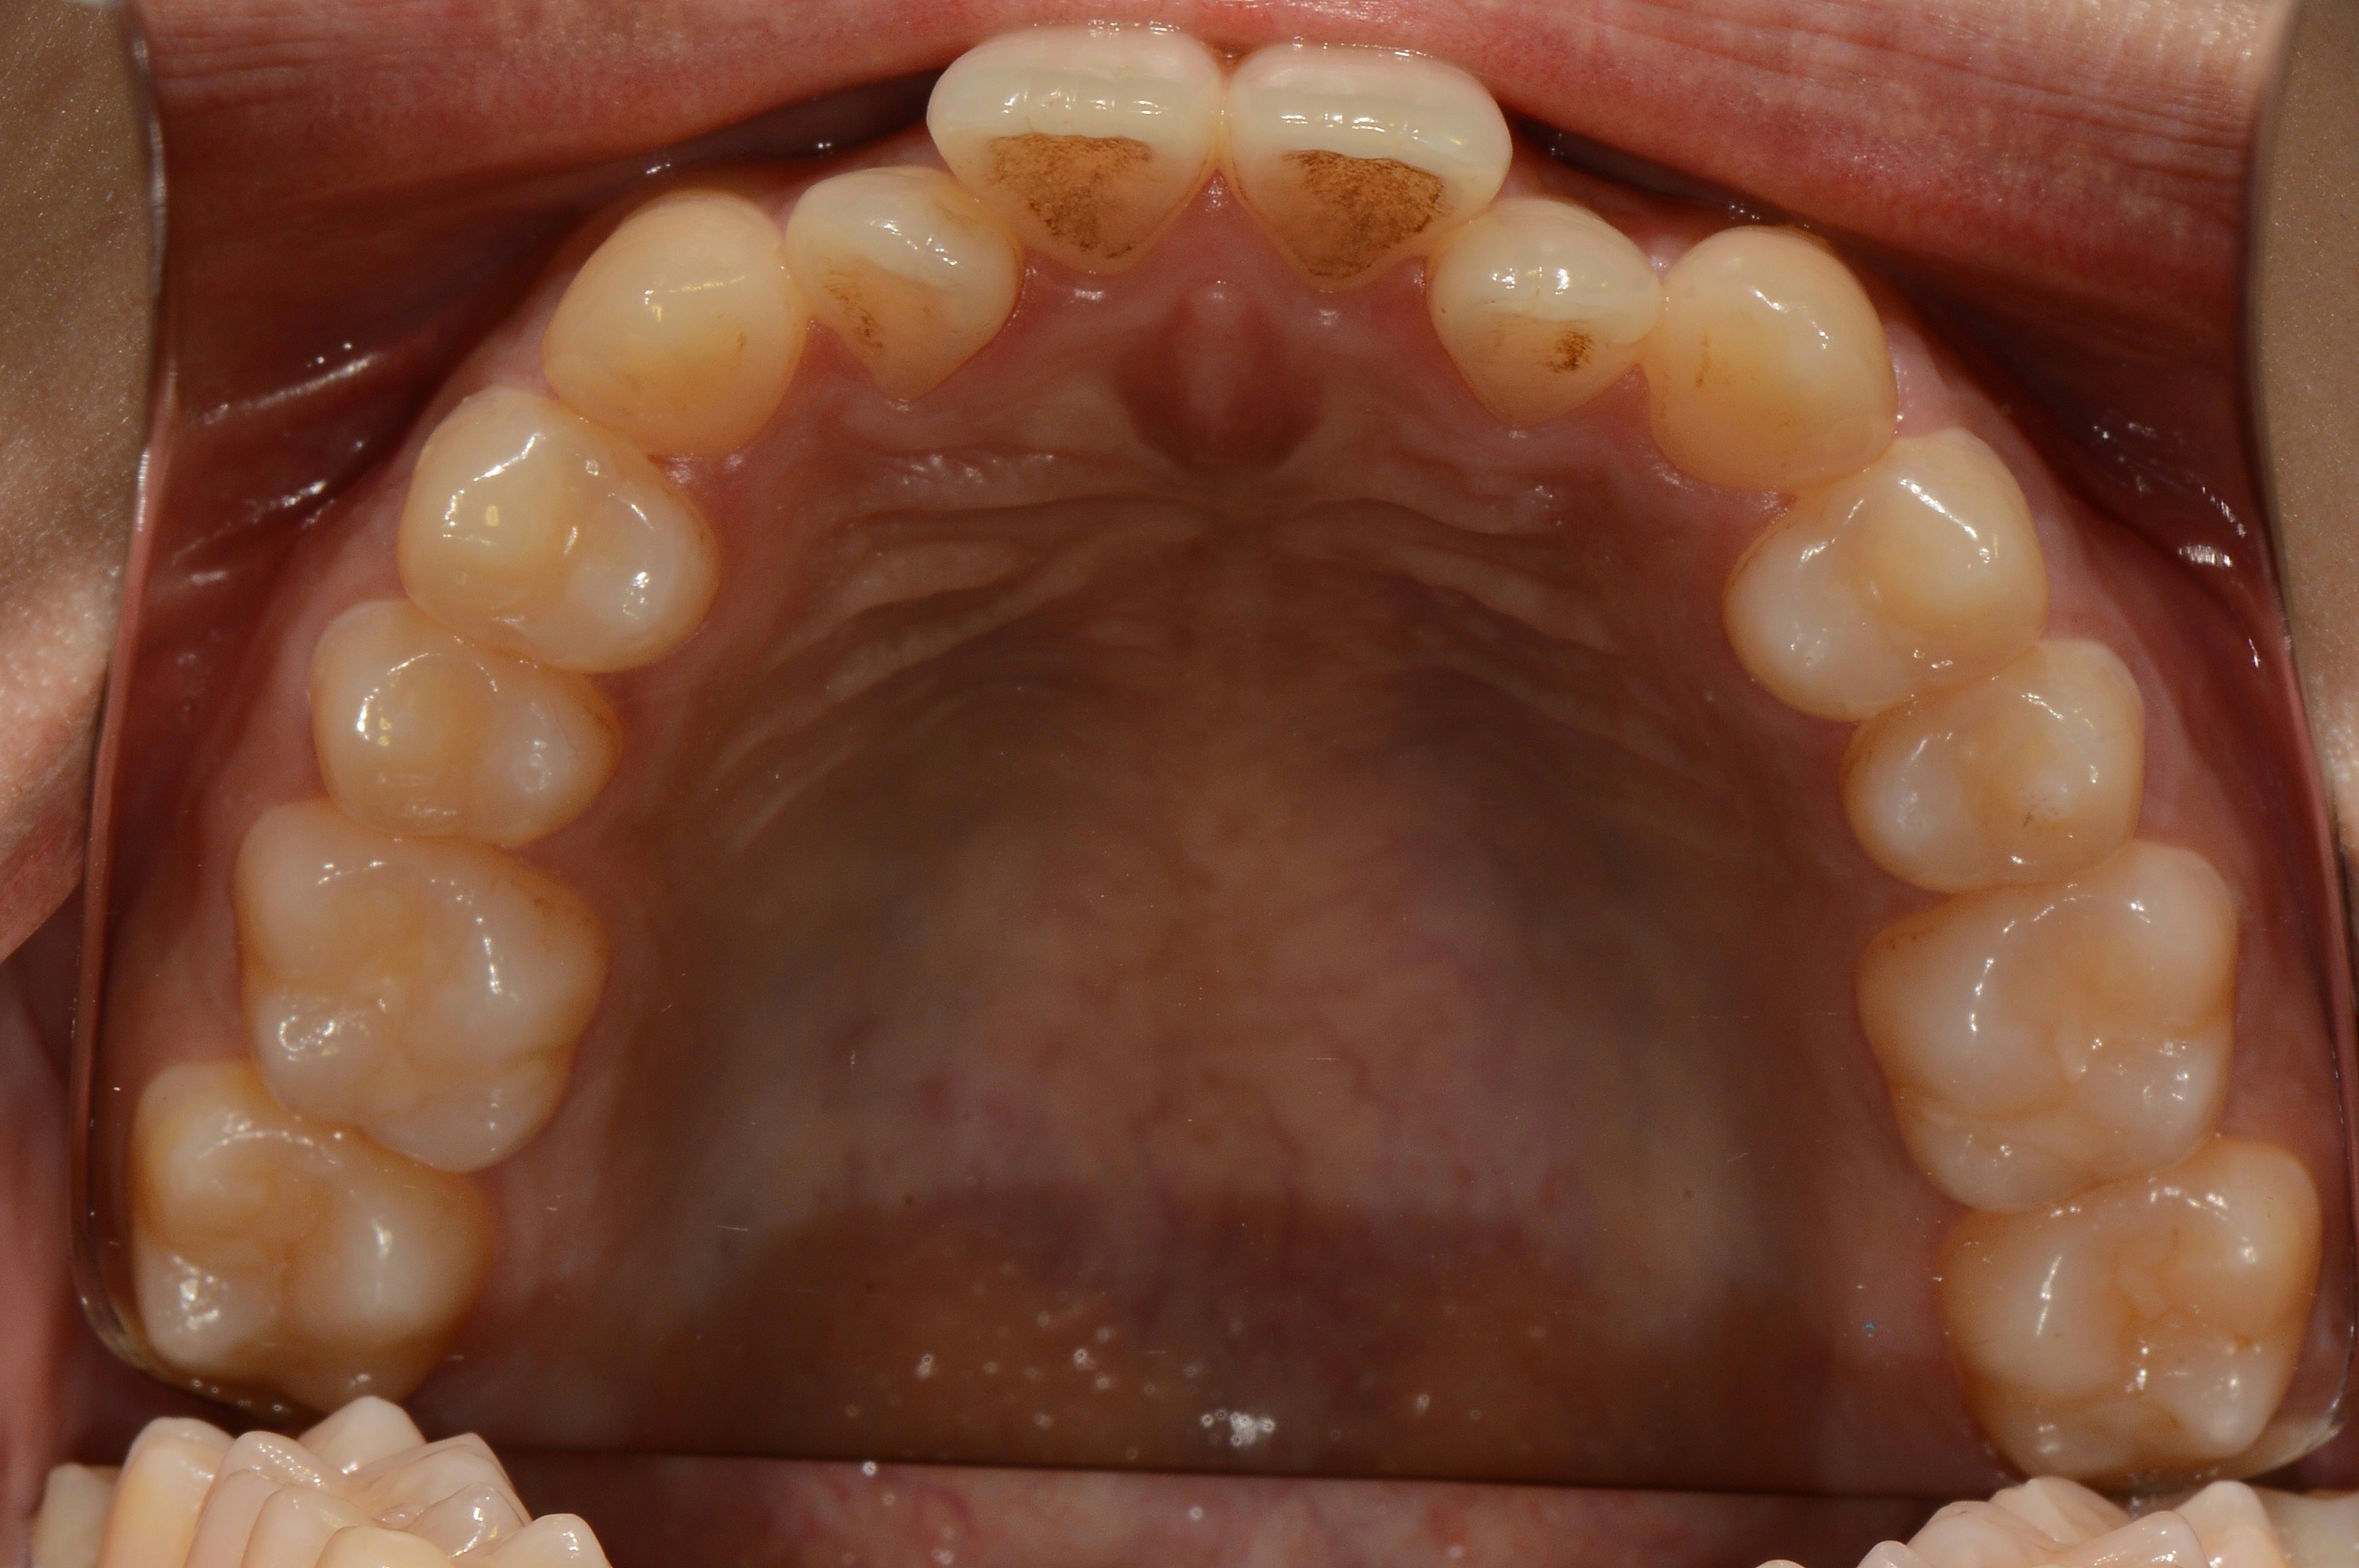

치료 전 사진입니다.